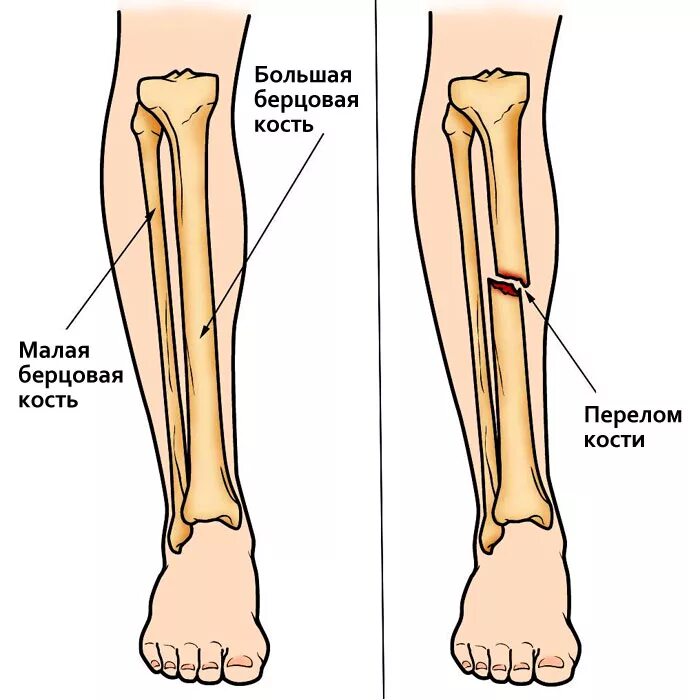

Перелом берцовых